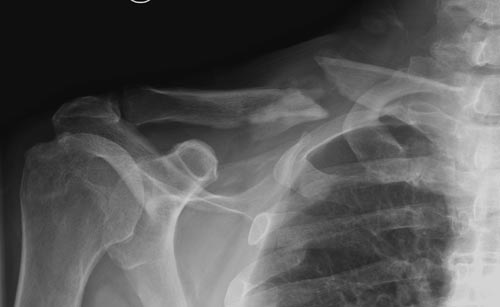

Болезненные ложные суставы надо оперировать, и здесь представлен случай

свежего болезненного ложного сустава, оперированного через 4 месяца.

Освобожден средний фрагмент и боковая компрессия лагированием, фиксация

пластиной..